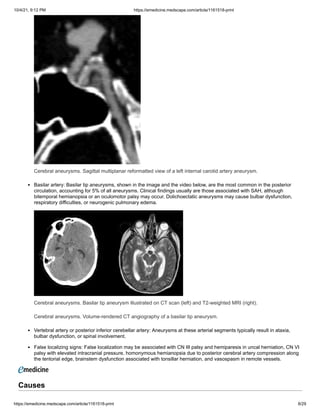

Cerebral aneurysms. Sagittal multiplanar reformatted view of a left internal carotid artery aneurysm.

Basilar artery: Basilar tip aneurysms, shown in the image and the video below, are the most common in the posterior

circulation, accounting for 5% of all aneurysms. Clinical findings usually are those associated with SAH, although

bitemporal hemianopsia or an oculomotor palsy may occur. Dolichoectatic aneurysms may cause bulbar dysfunction,

respiratory difficulties, or neurogenic pulmonary edema.

Cerebral aneurysms. Basilar tip aneurysm illustrated on CT scan (left) and T2-weighted MRI (right).

Cerebral aneurysms. Volume-rendered CT angiography of a basilar tip aneurysm.

Vertebral artery or posterior inferior cerebellar artery: Aneurysms at these arterial segments typically result in ataxia,

bulbar dysfunction, or spinal involvement.

False localizing signs: False localization may be associated with CN III palsy and hemiparesis in uncal herniation, CN VI

palsy with elevated intracranial pressure, homonymous hemianopsia due to posterior cerebral artery compression along

the tentorial edge, brainstem dysfunction associated with tonsillar herniation, and vasospasm in remote vessels.